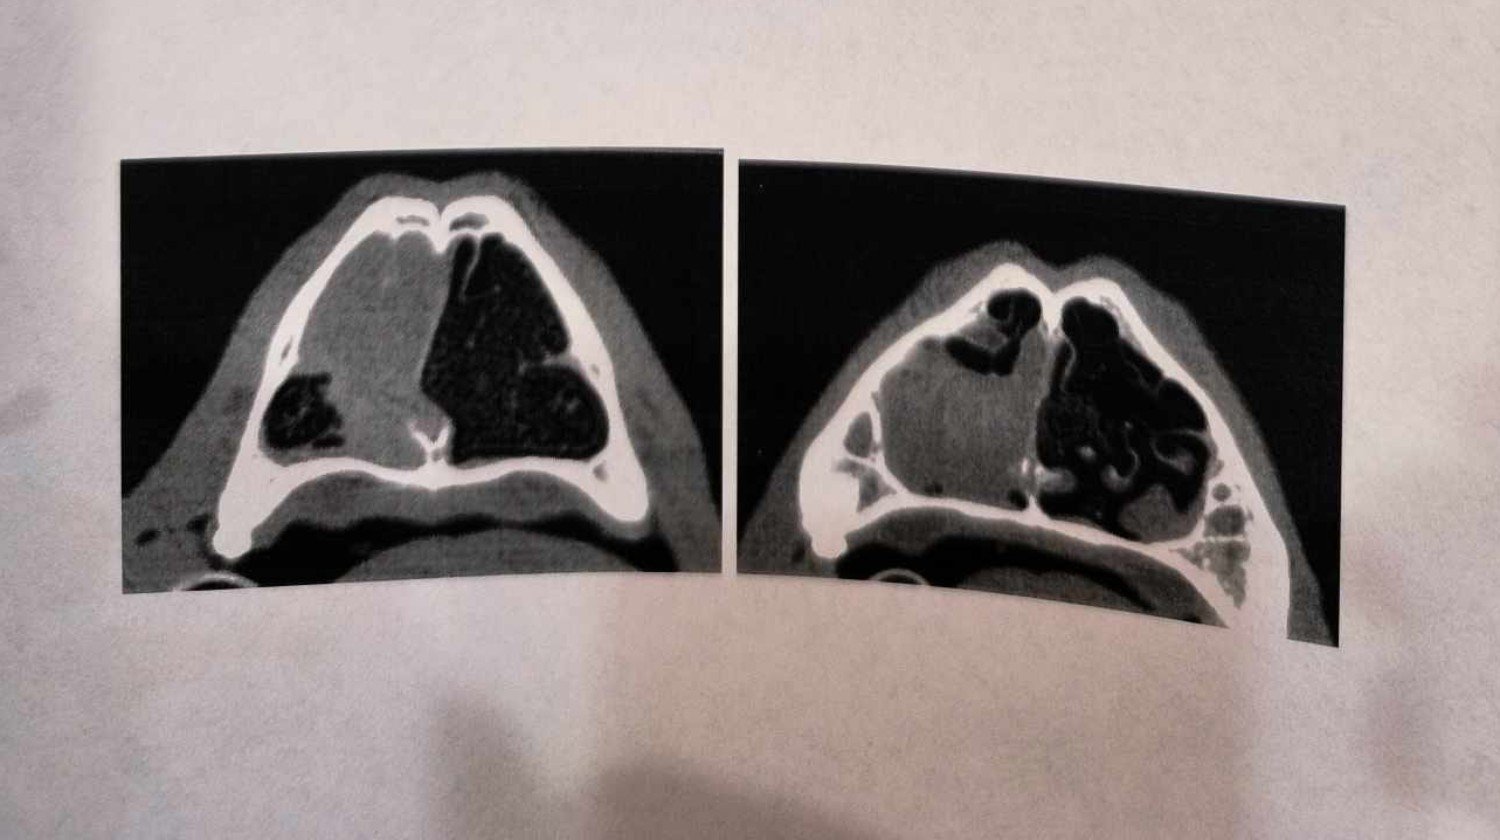

Pewnego dnia, w kojcu gminnym, niedaleko Włocławka znalazł się on, Bolek..nie znamy jego przeszłości, ani byłych opiekunów...Bolek został wstępnie określony na 2 lata, które później weterynarz zamienił na 8..Piesek zaszczepiony i wykastrowany..jego koledzy dawno adoptowani, a jego, z uwagi na brak przyszłego domu czekało schronisko o złej sławie, z którym gmina ma podpisaną umowę..By psiaka uchronić przed wywiezieniem, zawalczylismy o dom tymczasowy..zamieszkał u Joasi, która ma u siebie inne czworonogi, a mimo to, otworzyła serce dla smutnego psiaka, samotnie spędzającego czas w zimnym kojcu.. Będąc już na miejscu, kiedy myślano, że wszystko, co złe, już poza psiakiem..Bolek zachorował, odmawiał jedzenia, leciała mu krew z nosa..wykonano szereg badań. Bolek odwiedził też wielu specjalistów, dra Słodkiego, dra Krawczyka..wzięto m.in wycinek z nosa do badań histopatologicznych..i okazało się, że jest zmiana w zatokach przynosowych, może być łagodna, albo nowotworowa..żeby to stwierdzić psiak musi przejść kosztowny zabieg chirurgiczny..bez niego, jego komfort życia jest kiepski..pies nie może oddychać..Przy okazji, okazało się też, że na tułowiu, w okolicy łopatki powstał ropień, a w nim zadomowiły się dirofilarie... Niestety, zabieg i badania oraz leki dla Bolka, są bardzo kosztowne ...W sytuacji, kiedy pod opieką Asi są jeszcze inne, w tym chore zwierzęta podjęcie się operacji Bolka jest w tej chwili niemożliwe...Stąd wielka prośba o wsparcie i pomoc, o wpłaty..Wierzymy, że operacja planowana za miesiąc odbędzie się. Bardzo prosimy o wsparcie dla naszego czworonożnego przyjaciela.